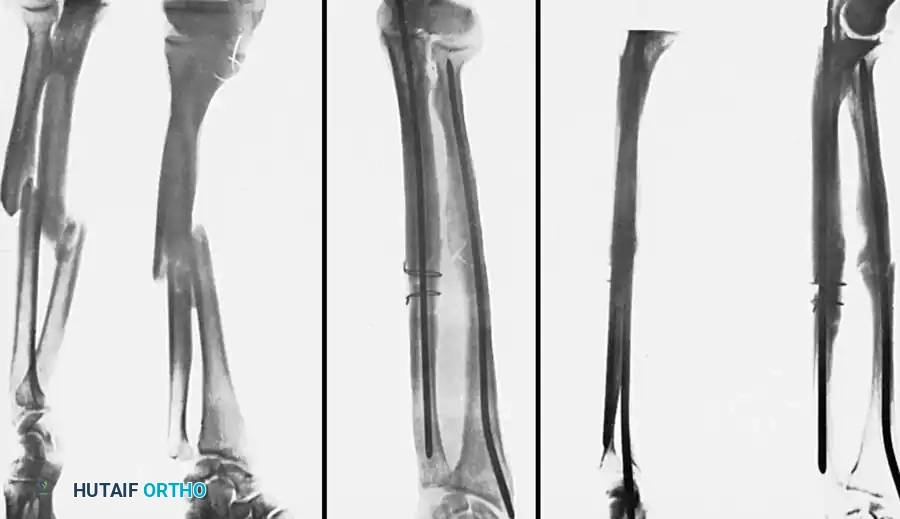

Fig. 54-55 Olecranon fracture repaired with long 6.5-mm AO cancellous screw and figure-of-eight tension band wire loop. Screw must engage cortex of diaphysis of ulna.

Fig. 54-56 A and B, Transverse olecranon fracture repaired with Kirschner wires and tension band technique. C, Double twist modification of wiring suggested by Weber and Vasey.